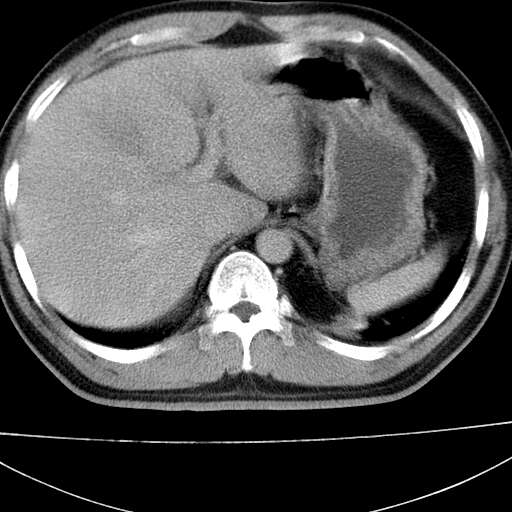

标题: CT21921:腹膜后腔肿物。患者男39Y。体检。增强扫描时间欠准

2、左下膈肌脚外缘结节状病变,与胸膜交界面呈锐角,胸膜下脂肪线可见,定位于肺内,考虑支气管囊肿或肺隔离征可能性大。

左膈肌连续性中断,左侧膈疝可能性大.

考虑左肺下叶后基底段肺隔离症?胸膜间皮瘤?

左膈肌连续性中断,左侧膈疝可能性大